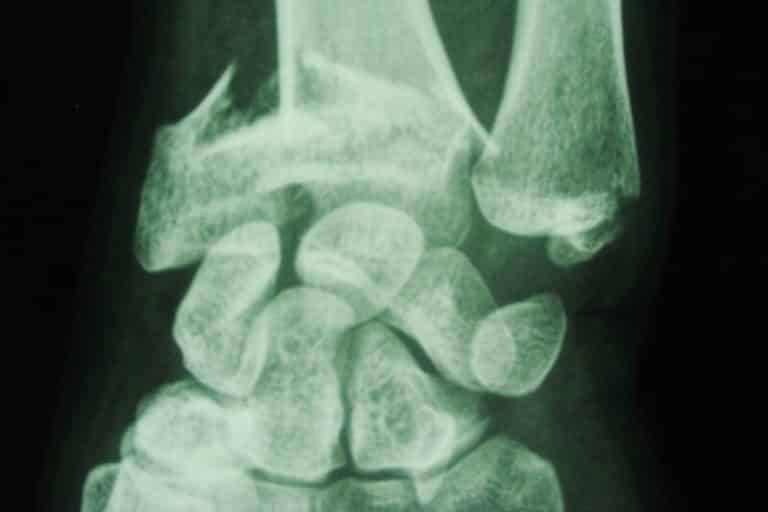

Fracture Du Poignet Gauche . les fractures du poignet localisées à l’extrémité inférieure du radius chez l’adulte sont très fréquentes. la fracture du poignet est généralement due à une chute sur une main tendue: cet article fait partie du dossier : Fracture du poignet chez l’adulte. les fractures du poignet sont généralement dues à une chute sur une main tendue. Quelles sont les principales causes des fractures du poignet ? Le radius se casse alors près du poignet, et l’extrémité cassée du radius est déplacée vers le Ces fractures peuvent généralement être identifiées sur des radiographies, mais une tomodensitométrie est parfois nécessaire. Combien de temps garder le plâtre ? c'est surtout l'extrémité du radius ou du scaphoïde qui se casse en cas de fracture au poignet. La plupart des fractures du poignet. Le poignet ne supporte pas le poids du corps et se brise. Il existe 2 types de traitement : douleurs et gonflement du poignet sont les symptômes les plus fréquents de la fracture du poignet. une fracture du poignet est une fracture de l’un des os de votre poignet.

Fracture Du Poignet Gauche Quelles sont les principales causes des fractures du poignet ? Combien de temps garder le plâtre ? Quelles sont les principales causes des fractures du poignet ? c'est surtout l'extrémité du radius ou du scaphoïde qui se casse en cas de fracture au poignet. une fracture du poignet est une fracture de l’un des os de votre poignet. cet article fait partie du dossier : La plupart des fractures du poignet. Ces fractures peuvent généralement être identifiées sur des radiographies, mais une tomodensitométrie est parfois nécessaire. douleurs et gonflement du poignet sont les symptômes les plus fréquents de la fracture du poignet. les fractures du poignet localisées à l’extrémité inférieure du radius chez l’adulte sont très fréquentes. Dans 50 % des cas,. la fracture du poignet est généralement due à une chute sur une main tendue: Le radius se casse alors près du poignet, et l’extrémité cassée du radius est déplacée vers le Le poignet ne supporte pas le poids du corps et se brise. Il existe 2 types de traitement : les fractures du poignet sont généralement dues à une chute sur une main tendue.